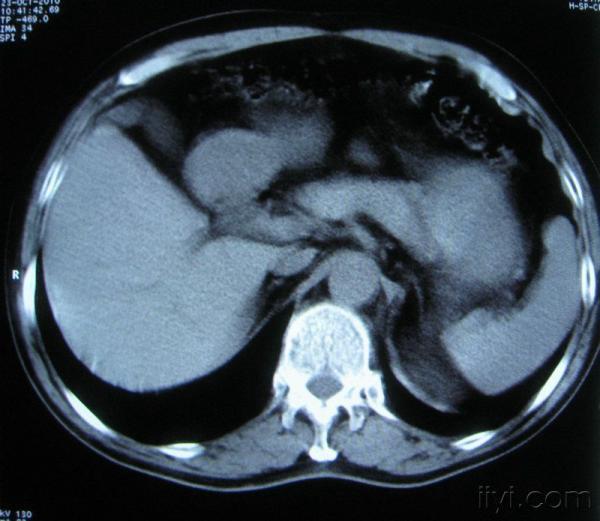

男。60岁,胸片示支气管炎治疗后复查CT。

根据位置考虑应该是淋巴结,密度不均,是因为肿大的淋巴结中心液化坏死

你指那个肯定是淋巴结,中央系坏死,这很常见,特别在双侧腹股沟会经常看到。这个双侧腋窝及纵隔见多发小淋巴结征。